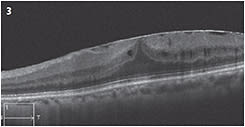

An ERM is thought to occur in the setting of vitreoschisis, which itself can occur secondary to an anomalous posterior vitreous detachment that involves “splitting” of the vitreous and some posterior vitreous remaining on the surface of the retina. This posterior vitreous acts as a scaffold for glial cells to proliferate and form an ERM (Figure 3). These membranes may not cause any visual symptoms — or they may cause metamorphopsia or blurred vision due to macular traction and retinal thickening.

Figure 3: OCT shows an epiretinal membrane with distortion of foveal anatomy and small intraretinal cysts with absence of VMA.